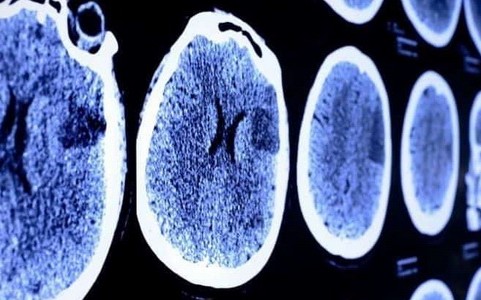

Terapię z wykorzystaniem komórek własnego szpiku kostnego pacjenta do leczenia stwardnienia rozsianego opracowali polscy naukowcy.